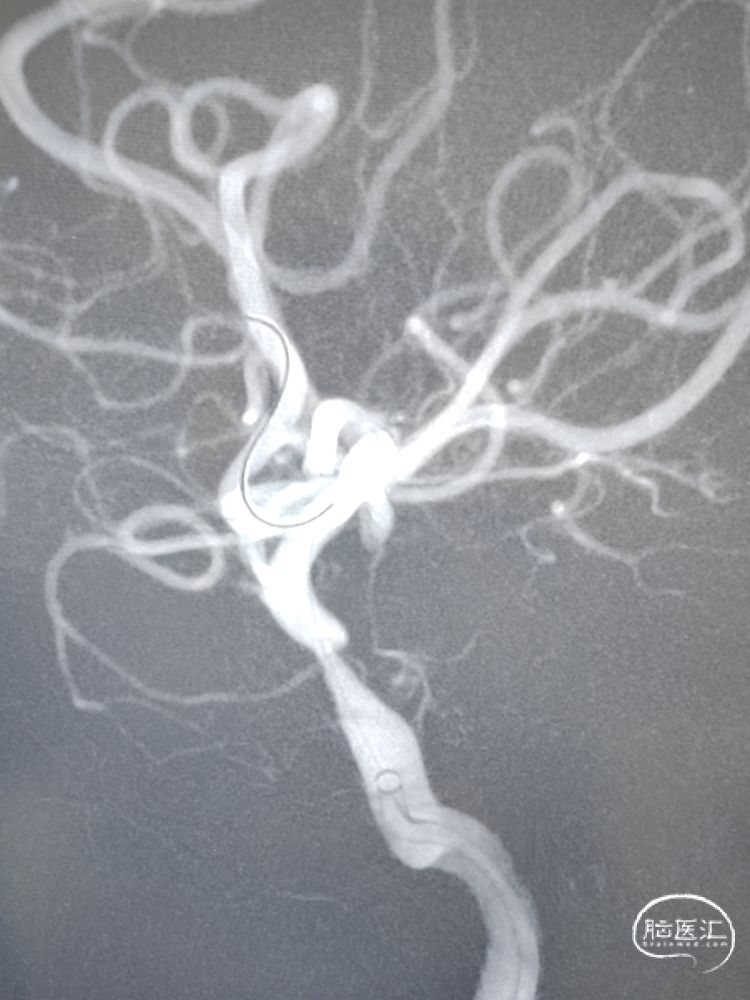

留置微导丝,撤出支架释放系统,观察10分钟后造影提示血流无异常,遂撤出微导丝。侧位、正位造影减影像和非减影像提示颈内动脉海绵窦段支架内和远端血流通畅,支架顺应血管贴壁良好;由于近端血流改善,后交通动脉充分显影。